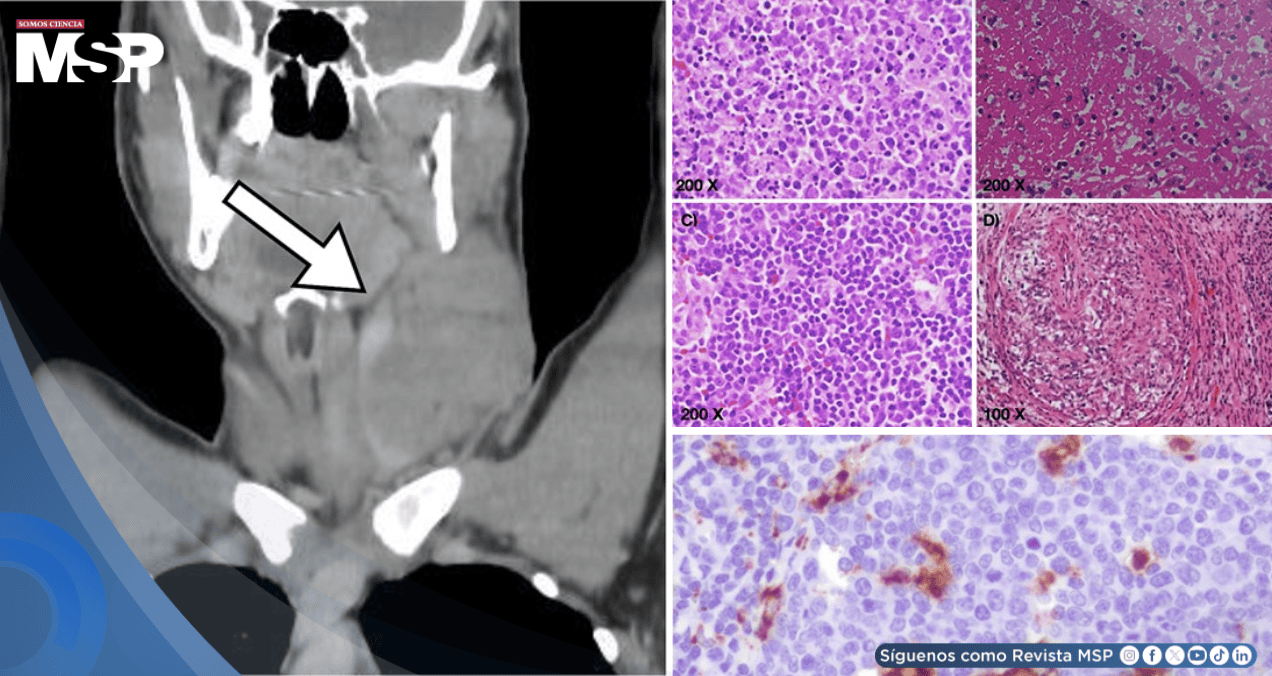

Posteriormente, una tomografía computarizada confirmó la presencia de ganglios agrandados no solo en el cuello, sino también en la región supraclavicular y el mediastino, hallazgos que generaron preocupación por enfermedades más graves como linfoma o tuberculosis.

Ante la persistencia de la masa y la sospecha clínica, se decidió realizar una biopsia del ganglio afectado. El estudio del tejido descartó la presencia de cáncer y reveló una inflamación característica conocida como linfadenitis histiocítica necrotizante. Pruebas especiales confirmaron el diagnóstico de la enfermedad de Kikuchi-Fujimoto, una afección rara y benigna del sistema inmunológico.

Los estudios de imagen y laboratorio fueron inespecíficos; solo la biopsia con inmunohistoquímica (CD68+, CD123+) permitió confirmar una linfadenitis necrotizante histiocítica no maligna, descartando linfoma o tuberculosis.